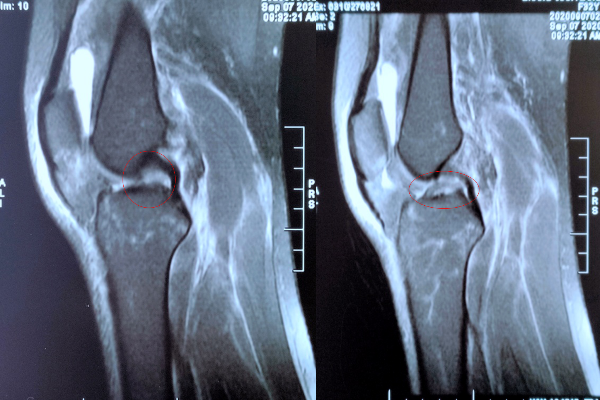

MRI可见:外侧半月板后角撕裂(红圈所示)